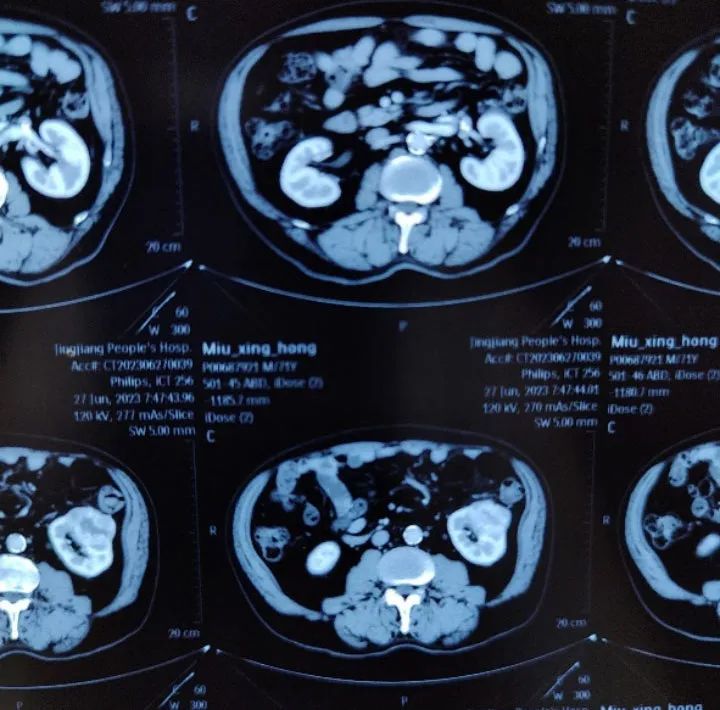

患者女性,34岁,因左肾肿瘤行左肾切除术,术后1年发现局部复发伴肺部转移。患者于2022年6月,因左肾血管平滑肌脂肪瘤在外院接受左肾切除术,2023年7月患者复查发现左侧腹膜后占位,2023-07-21外院超声造影:1.左肾切除术后;2.左侧腹膜后低回声团块,呈“不均匀性增强”(MT可能性大),2023-07-21外院肺部CT:双肺新增多发结节影,考虑转移瘤。2023-07-24在外院行超声引导下左侧腹腔肿物粗针穿刺活检术,病理回报:腹膜后淋巴结送检标本镜下见上皮样血管平滑肌脂肪瘤伴坏死,请结合临床。免疫组化结果: HMB45、MelanA阳性,Desmin少量阳性,CK-pan、CD10、Ihibin-a 阴性。目前诊断:1.左侧腹膜后上皮样血管平滑肌脂肪瘤;2.左肾切除术后。此次会诊的目的:下一步治疗方案?手术?化疗?靶向治疗?

影像科周秀秀主治医师:患者腹部CT影像显示:左侧腹膜后血管平滑肌脂肪瘤,肿瘤体积较大,直径达10cm以上,病灶中央可见坏死灶,同时肺部CT显示双肺新增多发结节影,考虑为转移瘤,提示该肿瘤进展较快,结合病理报告,考虑属于特殊类型的血管平滑肌脂肪瘤。